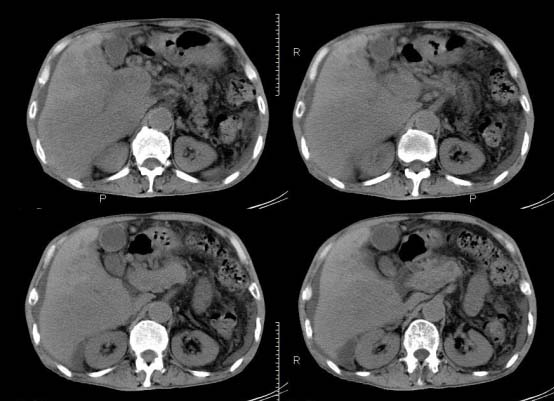

以下是引用杀毒软件在2010-3-30 18:11:00的发言:[br]考虑---hcc侵犯侵犯周围组织〔胰腺、胆管、肠系膜上动静脉〕伴门脉、下腔静脉癌栓形成、动-静脉瘘、肝门、腹腔动脉周围淋巴结转移可能性大、腹水。

以下是引用pujunzhi在2010-3-31 8:45:00的发言:[br]支持 肝癌并多发肝内转移,胰头、肝门、腹腔动脉周围淋巴结转移,下腔静脉癌栓形成,肝硬化、腹水。

以下是引用jsgdoctor在2010-3-30 20:42:00的发言:[br]考虑---hcc侵犯侵犯周围组织〔胰腺、胆管、肠系膜上动静脉〕伴门脉、下腔静脉癌栓形成、动-静脉瘘、肝门、腹腔动脉周围淋巴结转移可能性大、腹水。